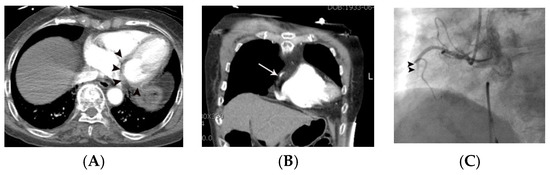

Figure 1.

Representative case, demonstrating probable MPD in a 69-year-old male with acute chest pain. Subendocardial or transmural hypoattenuation (arrowheads in (A–C)) was demonstrated on the multiple non-gated axial CT images along the left anterior descending coronary territory (i.e., antero-septum and the left ventricular apex). Note that attenuation of the mid-left anterior descending coronary artery (arrow in (D)) is low compared to the right coronary artery and left circumflex coronary artery (arrowheads in (D)), suggesting critical narrowing or occlusion of the left anterior descending coronary artery. Critical narrowing in the proximal left anterior descending coronary artery was confirmed on subsequent coronary angiography (arrow in (E)).